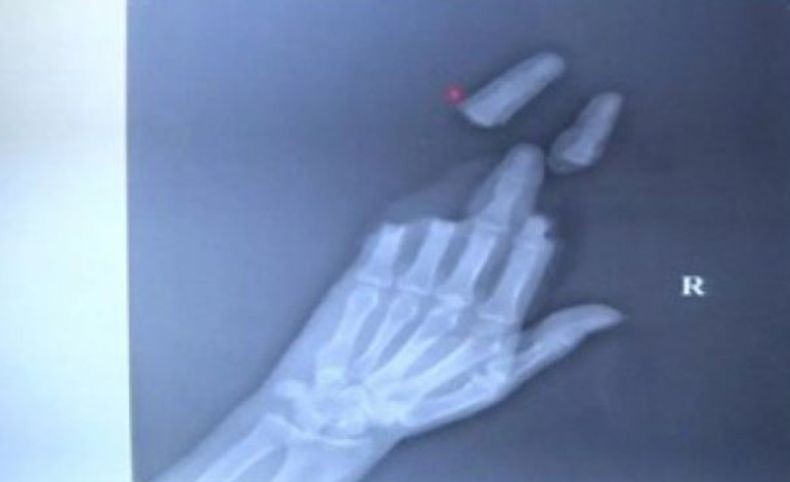

Tiga jari pria di China terpotong saat bermain layang-layang (Foto: SCMP)

BEIJING, iNews.id - Pria di Kota Nantong, Provinsi Jiangsu, China, mengalami nasib nahas saat bermain layang-layang besar, Selasa (9/4/2019). Tiga jarinya terpotong oleh benang layang-layang.

Keduanya menjalani operasi di Rumah Sakit Bedah Tulang Nantong. Beruntung, tiga jari yang terpotong itu bisa disambung kembali oleh dokter dan telapak tangan yang tersayat bisa dijahit dalam operasi yang berlangsung 16 jam.